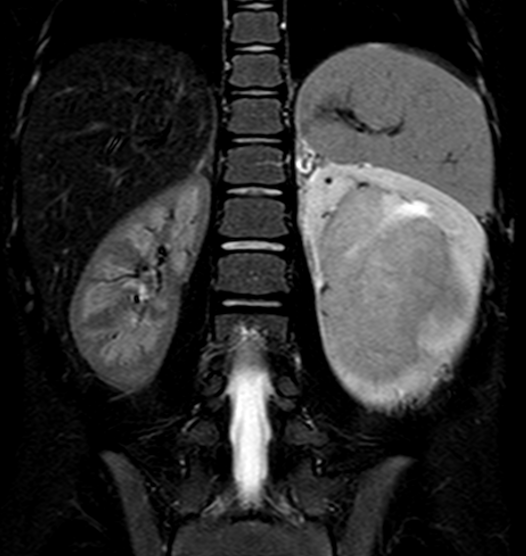

![]() MRI snímek zachycující nefroblastom levé ledviny u šestileté pacientky | |